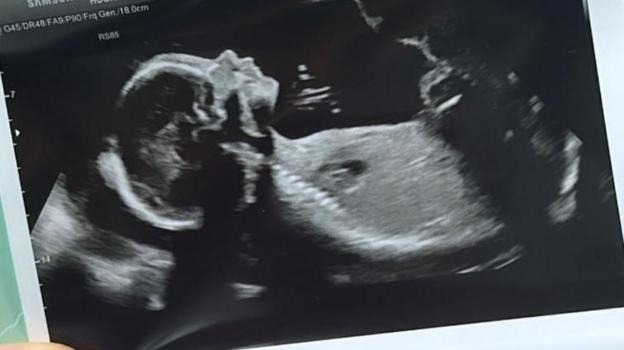

Everything had been fine during her pregnancy until the final weeks.

At 35 weeks pregnant, there was concern that her baby boy had stopped growing, and she was monitored daily.

In November 2024, the family received news no prospective parent wants to hear.

"I found out when I was 37 and a half weeks that Twm had died in the womb. They failed to find his heartbeat," she said.